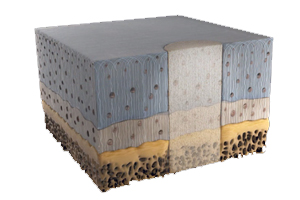

AgNovos Healthcare’s AGN1 local osteo-enhancement procedure small volume (LOEP SV) contains a calcium-based resorbable tri-phasic implant material formulated to couple the pace of resorption to bone formation, allowing treated vertebrae immediate, substantial protection. The AGN1 LOEP SV Kit is an investigational device intended to minimally-invasively treat painful but stable vertebral compression fractures often caused by bone loss associated with osteoporosis. The kit contains the instruments and components necessary to prepare the fractured vertebral body for injection. The device is thought to give clinicians a new tool to treat stable vertebral compression fractures in a more biologically-congruent fashion. A kit is already approved in Europe for larger volume applications at other anatomical sites. AgNovos received FDA Breakthrough designation for the kit in March 2020.

CartiHeal’s Agili-C implant is intended to treat cartilage lesions in both arthritic and non-arthritic joints. The implant is CE Marked for use in cartilage and osteochondral defects, and has been implanted in more than 500 patients with knee, ankle and toe cartilage lesions in a series of clinical trials in Europe and Israel. It was granted FDA Breakthrough designation in October 2020 and is the subject of an Investigational Device Exemption clinical study to evaluate the Agili-C implant compared with microfracture and debridement, the current standard of care. Final study results are expected in 2021.

Chondro-Gide collagen membrane is used in a single-step cartilage repair technique. The highly purified collagen membrane leverages the body’s own healing potential. It is used with bone marrow stimulation to treat defects. More than 10 years of clinical success in Europe have shown the product to be a cost-effective single surgery treatment for repairing lesions with bone marrow stimulation techniques.

Chondro3 is currently in development as a biomimetic graft for osteochondral lesions. The three-layered, proprietary collagen-based biodegradable matrix can be delivered in a single procedure, in an outpatient setting and at an affordable price. Chondro3 is designed to provide a scaffold for cellular and tissue in-growth and osteochondral defect repair at the site of lesion, supporting biomimetic repair of both cartilage and bone. The designation was granted in February 2021.